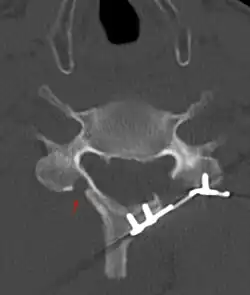

CT scan of Laminoplasty of cervical vertebra